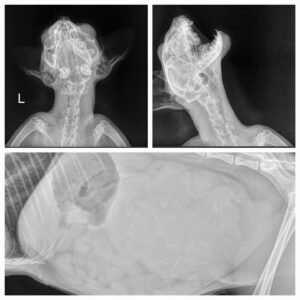

Rumpel

Und jetzt steht nicht nur seine Welt Kopf! Oft kommen Tiere zu uns, die wirklich dringend Hilfe benötigen. Tiere, die...